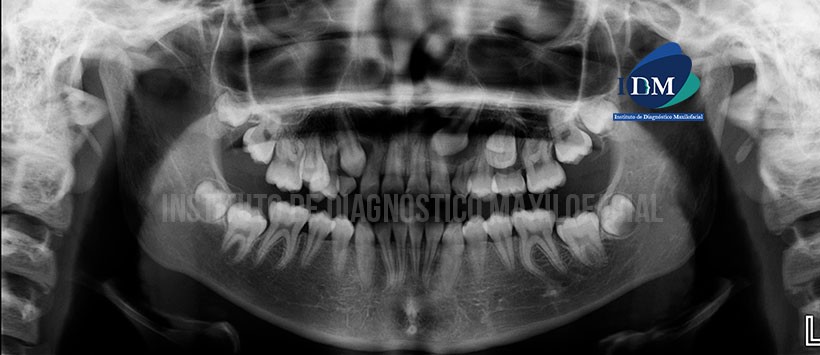

Paciente de sexo femenino con 13 años de edad acude al instituto de Diagnóstico Maxilofacial para evaluación imagenológica debido a la ausencia clínica de piezas permanentes en el maxilar superior.

A la evaluación panorámica se parecía una falta de espacio para la correcta erupción e las piezas permanentes, terceras molares en evolución intraósea y remanentes dentarios deciduos. Siendo lo mas resaltante que las piezas 13, 23 y 25 todavía no han logrado erupcionar, presentando un aparente aumento del espacio pericoronario. (Figura 1)